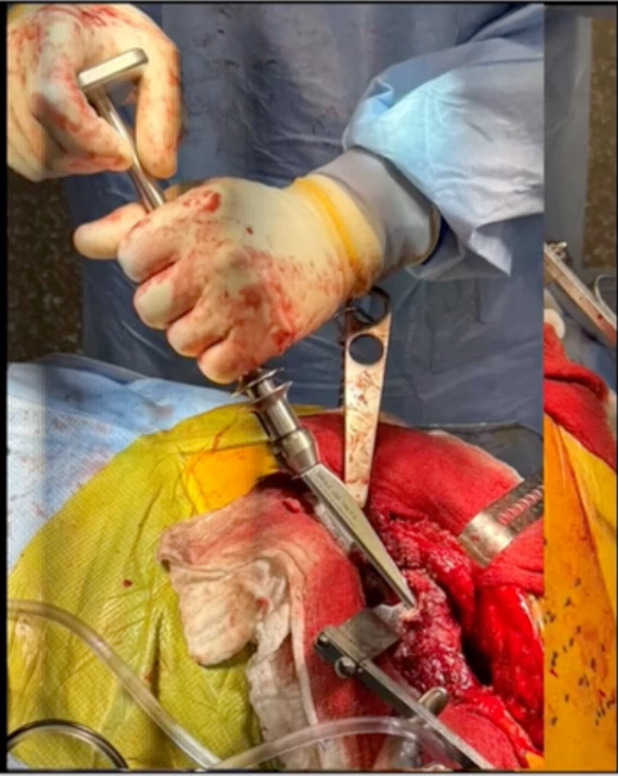

This is an example of the Watson going around the shoulder of the implant. (Figure 7)

It’s a nice tool until you crack the trochanter then, and maybe it’s not so. Nevertheless, these tools are great.